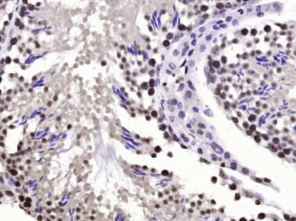

多聚甲醛固定,石蜡包埋(小鼠睾丸);经柠檬酸钠缓冲液(pH6.0)煮沸15min后获得抗原;用3%过氧化氢阻断内源性过氧化物酶20分钟;阻断缓冲液(正常山羊血清)37℃30min;用(BPTF)多克隆抗体进行抗体孵育在4°C下1:200整晚未结合的全身,然后根据SP试剂盒(兔子)说明和DAB染色进行操作。